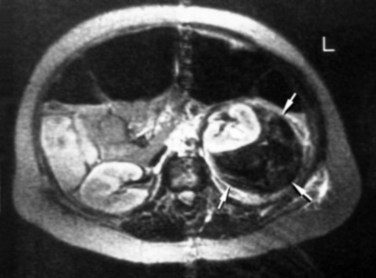

). Renal tubules often contain blood cell casts, and the tubular cells may show ischemic changes. In the setting of a more severe injury, complete necrosis of the endothelium and vascular smooth muscle may result. A typical clinical dose of 2000 shockwaves with the Dornier HM3 lithotripter, operated at 24 kV with shockwaves delivered at 2 Hz produces a lesion measuring 5% to 6% of the functional renal volume (Fig. 48–28).

Figure 48–28 Shockwave lithotripsy–treated and control kidneys imaged by positron emission tomographic scanning before and immediately after treatment with 3500 shockwaves to the lower pole, at level six, with a DoLi 50 device. The site of F2 (lower pole) on the shocked kidney shows a 50% reduction of renal blood flow (arrow).